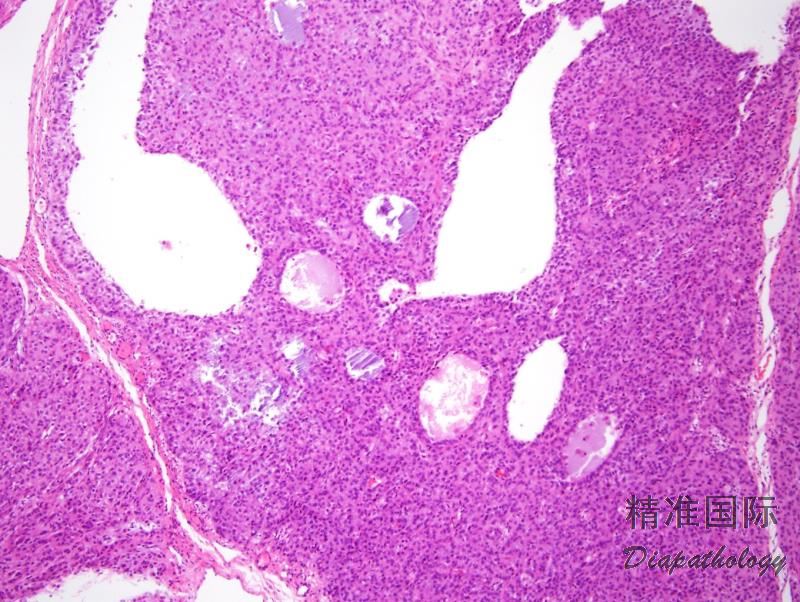

镜下典型表现为肿瘤细胞弥漫或结节状分布,其间穿插大小和形状不一的滤泡,但也可以是规则的圆形和卵圆形滤泡;

滤泡腔内含有嗜酸性,偶尔为嗜碱性分泌物,大约 2/3 的病例呈黏液卡红染色阳性;

滤泡内衬粒层细胞,细胞层数不同使得滤泡壁薄厚不一,周围可有卵泡膜细胞围绕,经常可见滤泡衬覆的粒层细胞与周围卵泡膜细胞区融合;

有时可见粒层细胞衬覆于假乳头结构;